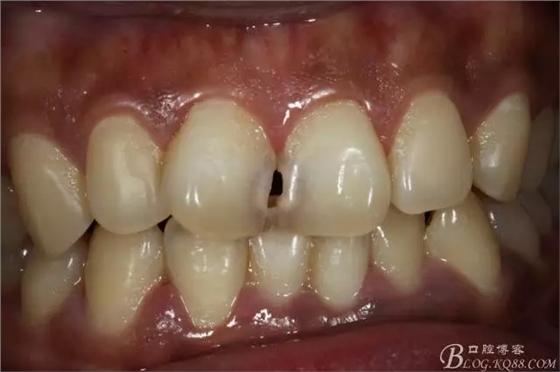

2012年2月接診是的情況

去腐備洞后